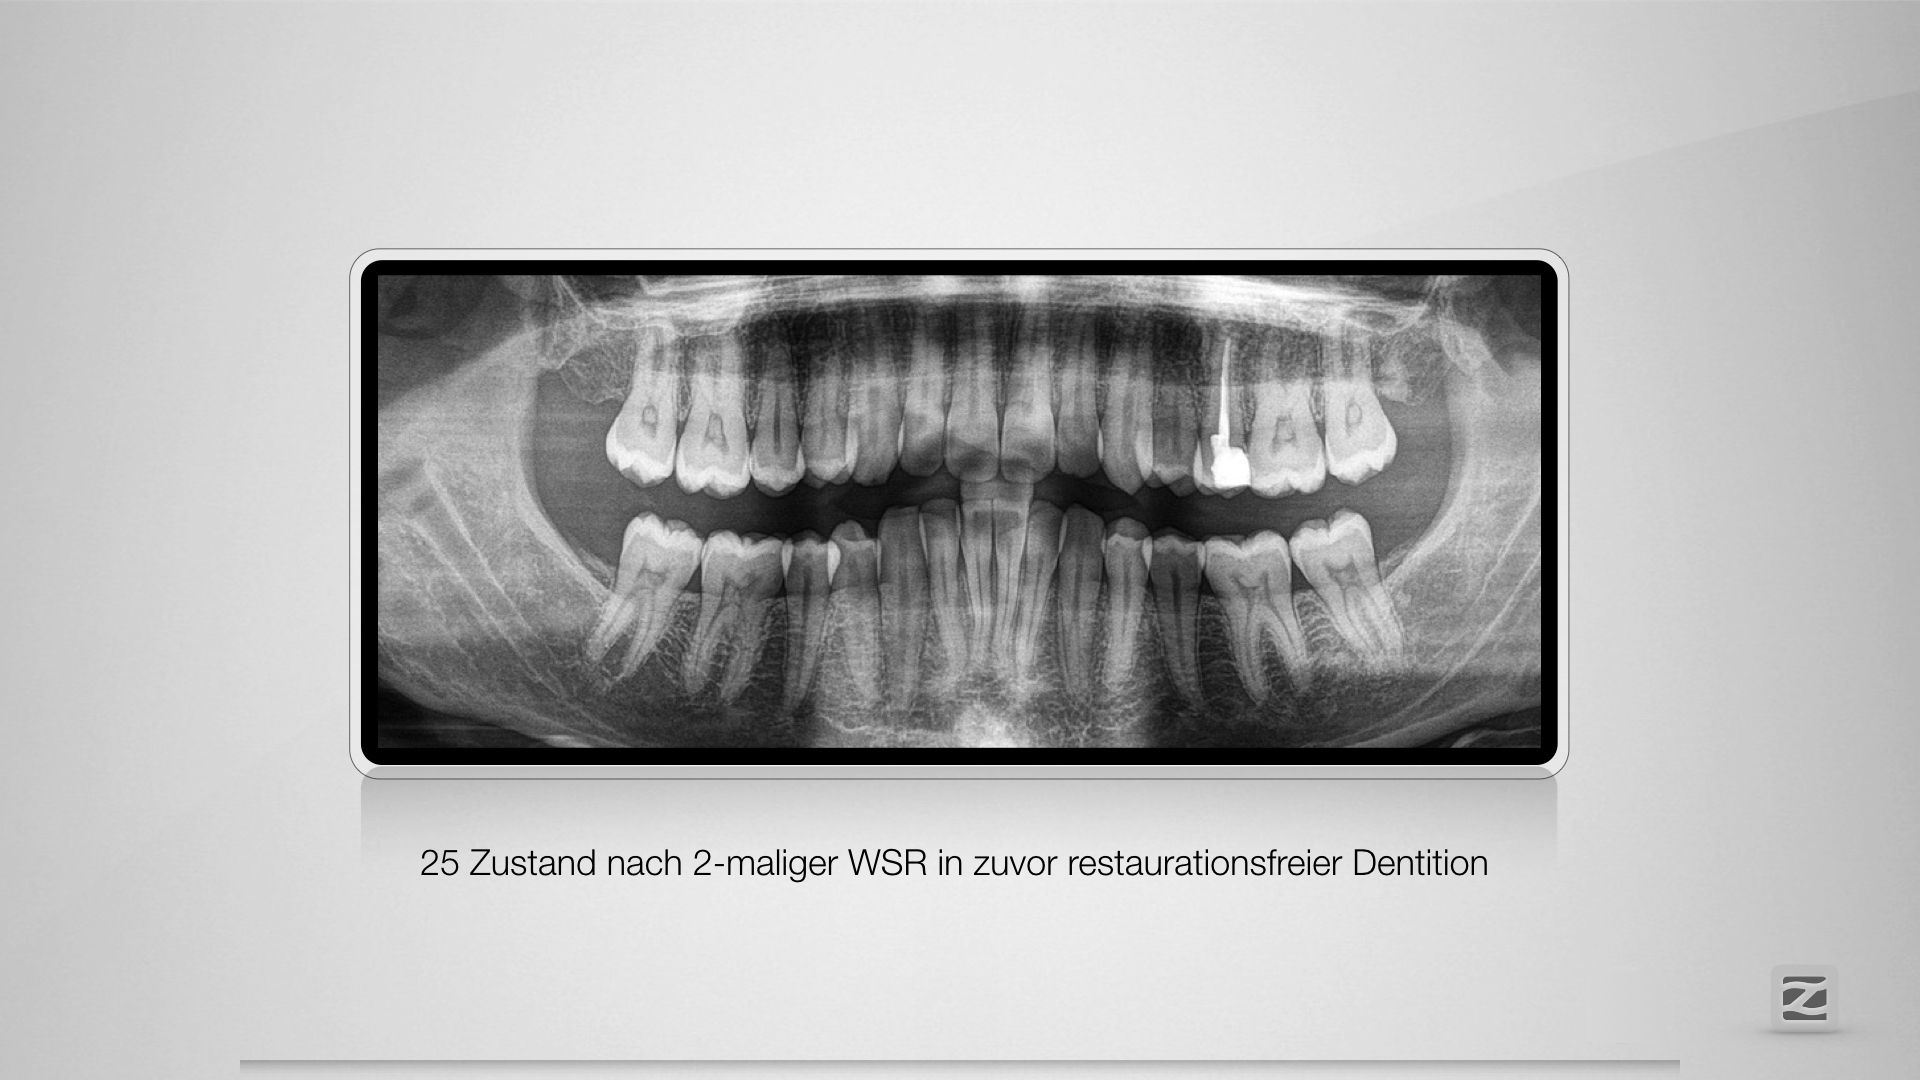

Fremdschämen